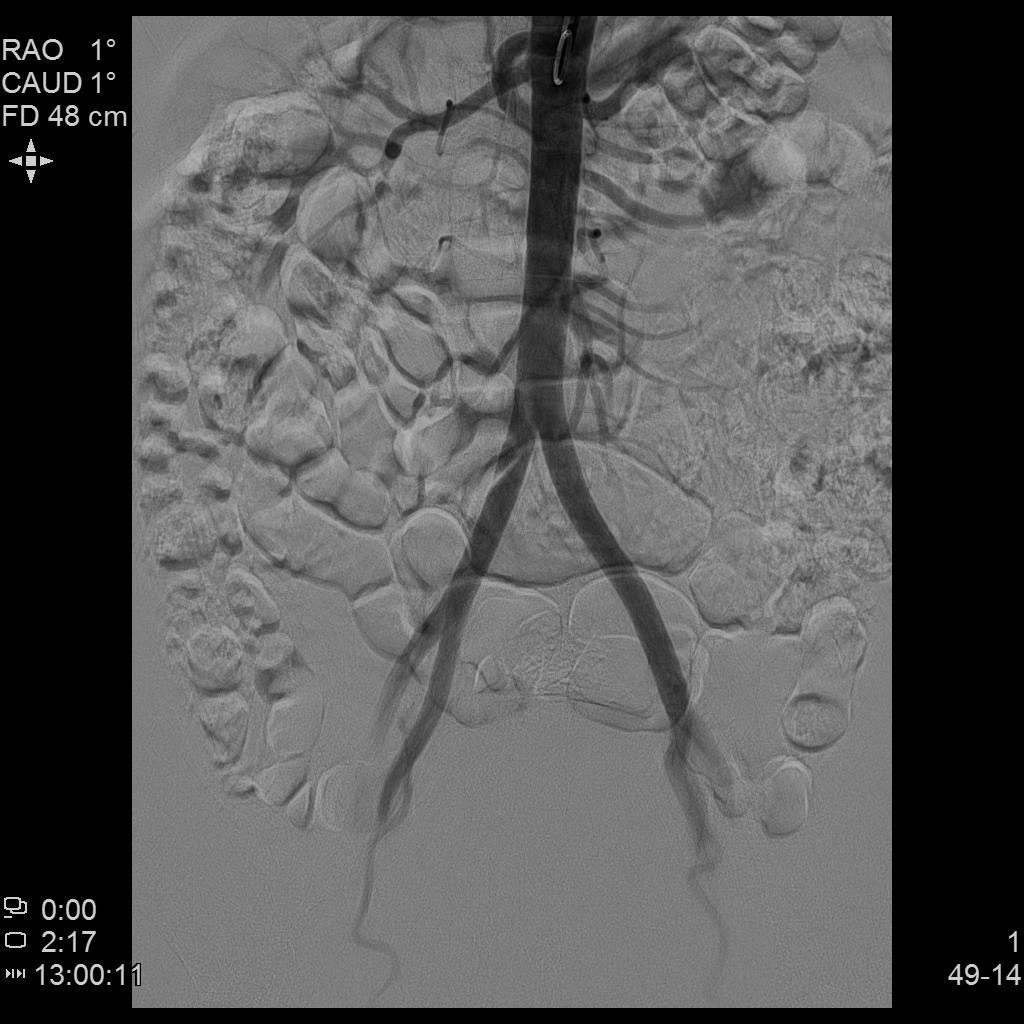

- 插管至右侧髂内动脉造影,显示右侧子宫动脉

- 插管至右侧子宫动脉,显示子宫右侧病灶情况

右侧子宫动脉造影

腹主动脉造影

左侧子宫造影